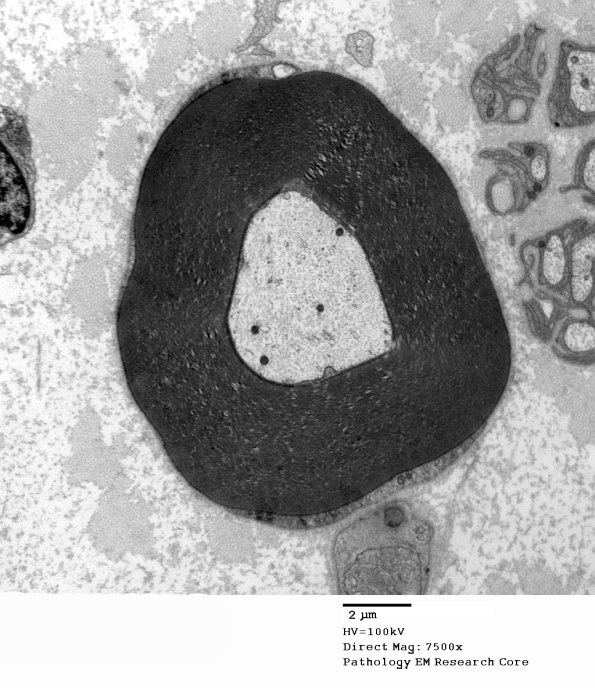

A peculiar hypermyelinated axon represents unusual myelinopathy. (electron micrograph)